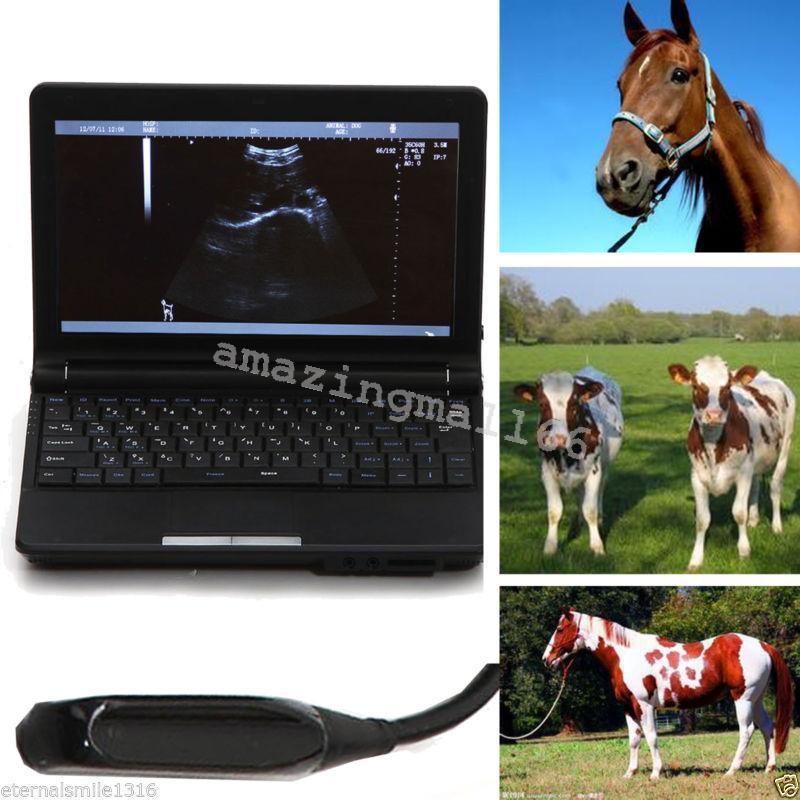

DIAGNOSTIC ULTRASOUND MACHINES FOR SALE

Veterinary vet Full Digital Laptop Ultrasound Scanner Micro-Convex Probe 3D Sale 190891712110

Sale price$ 1,922.89

Regular price$ 2,344.99